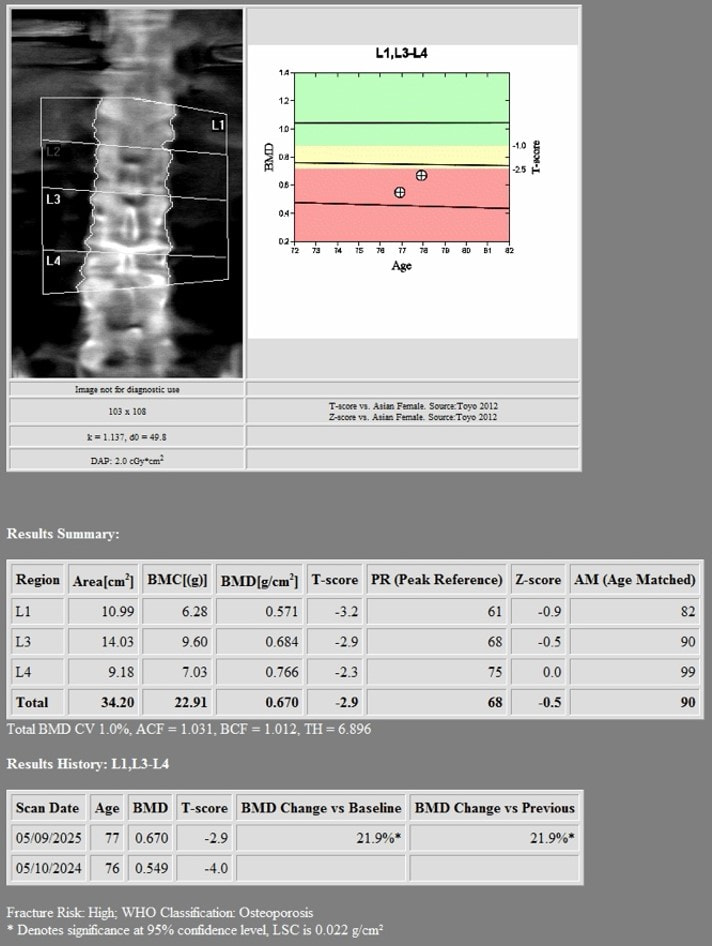

1st DXA Scan (Before Romosozumab treatment)

2nd DXA Scan (1 year after romosozumab treatment)

Hologic Horizon W

- LSC AP Spine 0.022 g/cm2

- LSC Neck of Femur 0.028 g/cm2

- LSC Total Hip 0.027 g/cm2

Changes in BMD after completing 1 year of Romosozumab

- Lumbar Spine = +0.121 g/cm2 (22.04%)

- Neck of Femur = +0.03 g/cm2 (6.86%)

- Total Hip = +0.049 g/cm2 (7.98%)

There was an increase in the BMD after she underwent 1 year of treatment with Romosozumab:

- Lumbar Spine: +0.121 g/cm2 (22.04%, LSC 0.022)

- Neck of Femur: +0.03 g/cm2 (6.86%, LSC 0.028)

- Total Hip: +0.049 g/cm2 (7.98%, LSC 0.027)

All the increases in these three parameters were higher than the respective LSC.

- DXA scan showed that the changes in BMD after completing 1 year of romosuzumab was: